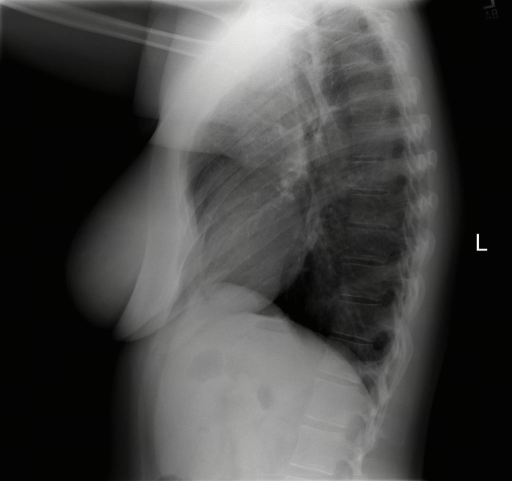

While anatomical reasoning provides the logical framework, visual limitations can hinder fine-grained detection. To address this, we integrated Think with Image [67, 22] design, enabling the model to perform secondary operations—such as rotating or zooming in—to facilitate a deeper understanding of visual information. This capability holds tremendous potential in medical imaging; for instance, zooming in on affected regions allows the model to perform granular inspection. Through exploration of tools in the multimodal domain, we identified Zoom in and Rotate as the most valuable primitives: the former is primarily designed for identifying subtle lesions in affected regions, while the latter assists with maintaining spatial orientation during the interpretation of complex medical images.

The training dataset is built mainly from radiology imaging data (e.g., X-rays, CT scans, MRI) and public de-identified radiology datasets, which include pathological/normal cases, metadata and expert annotations. Given the varying diagnostic complexity and tool utility of raw radiology data, a two-stage filtering pipeline is adopted to create an effective RL training set: